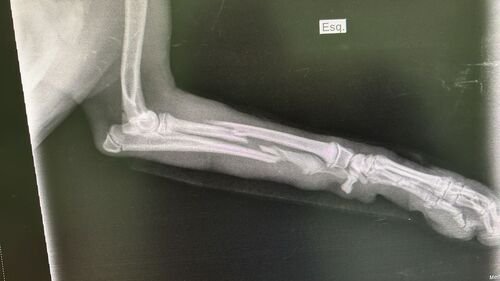

Pantera tem apenas 06 meses de vida e foi vítima de atropelamento e restou poli traumatizada (fraturas expostas nas duas patinhas traseiras, fratura na pelve e na patinha da frente).Seus tutores não tem condições de arcar com todos os custos do tratamento e cirurgias necessárias.